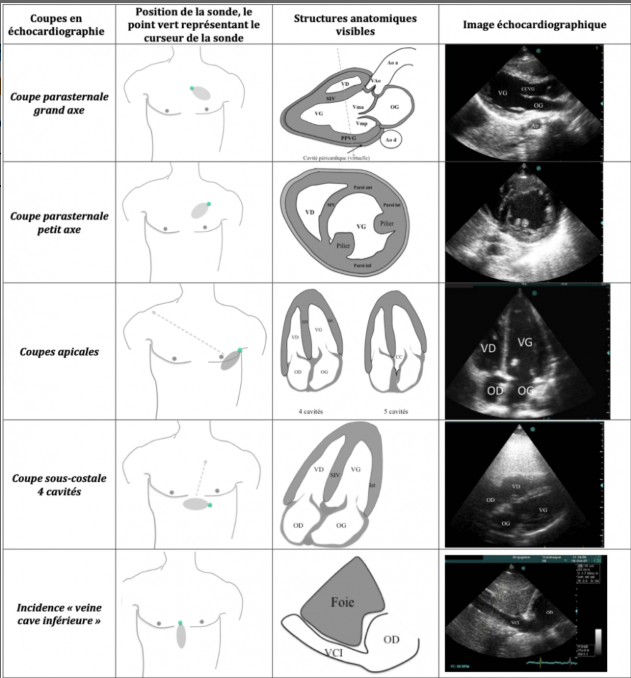

Pour chacune des coupes dire à quelle coupe échographique ça correspond